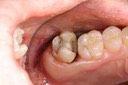

Chris Woo #30 pre-op

Chris Woo #30 caries removal

Chris Woo #30 prep

Chris Woo #30 try in

Chris Woo #30 finish